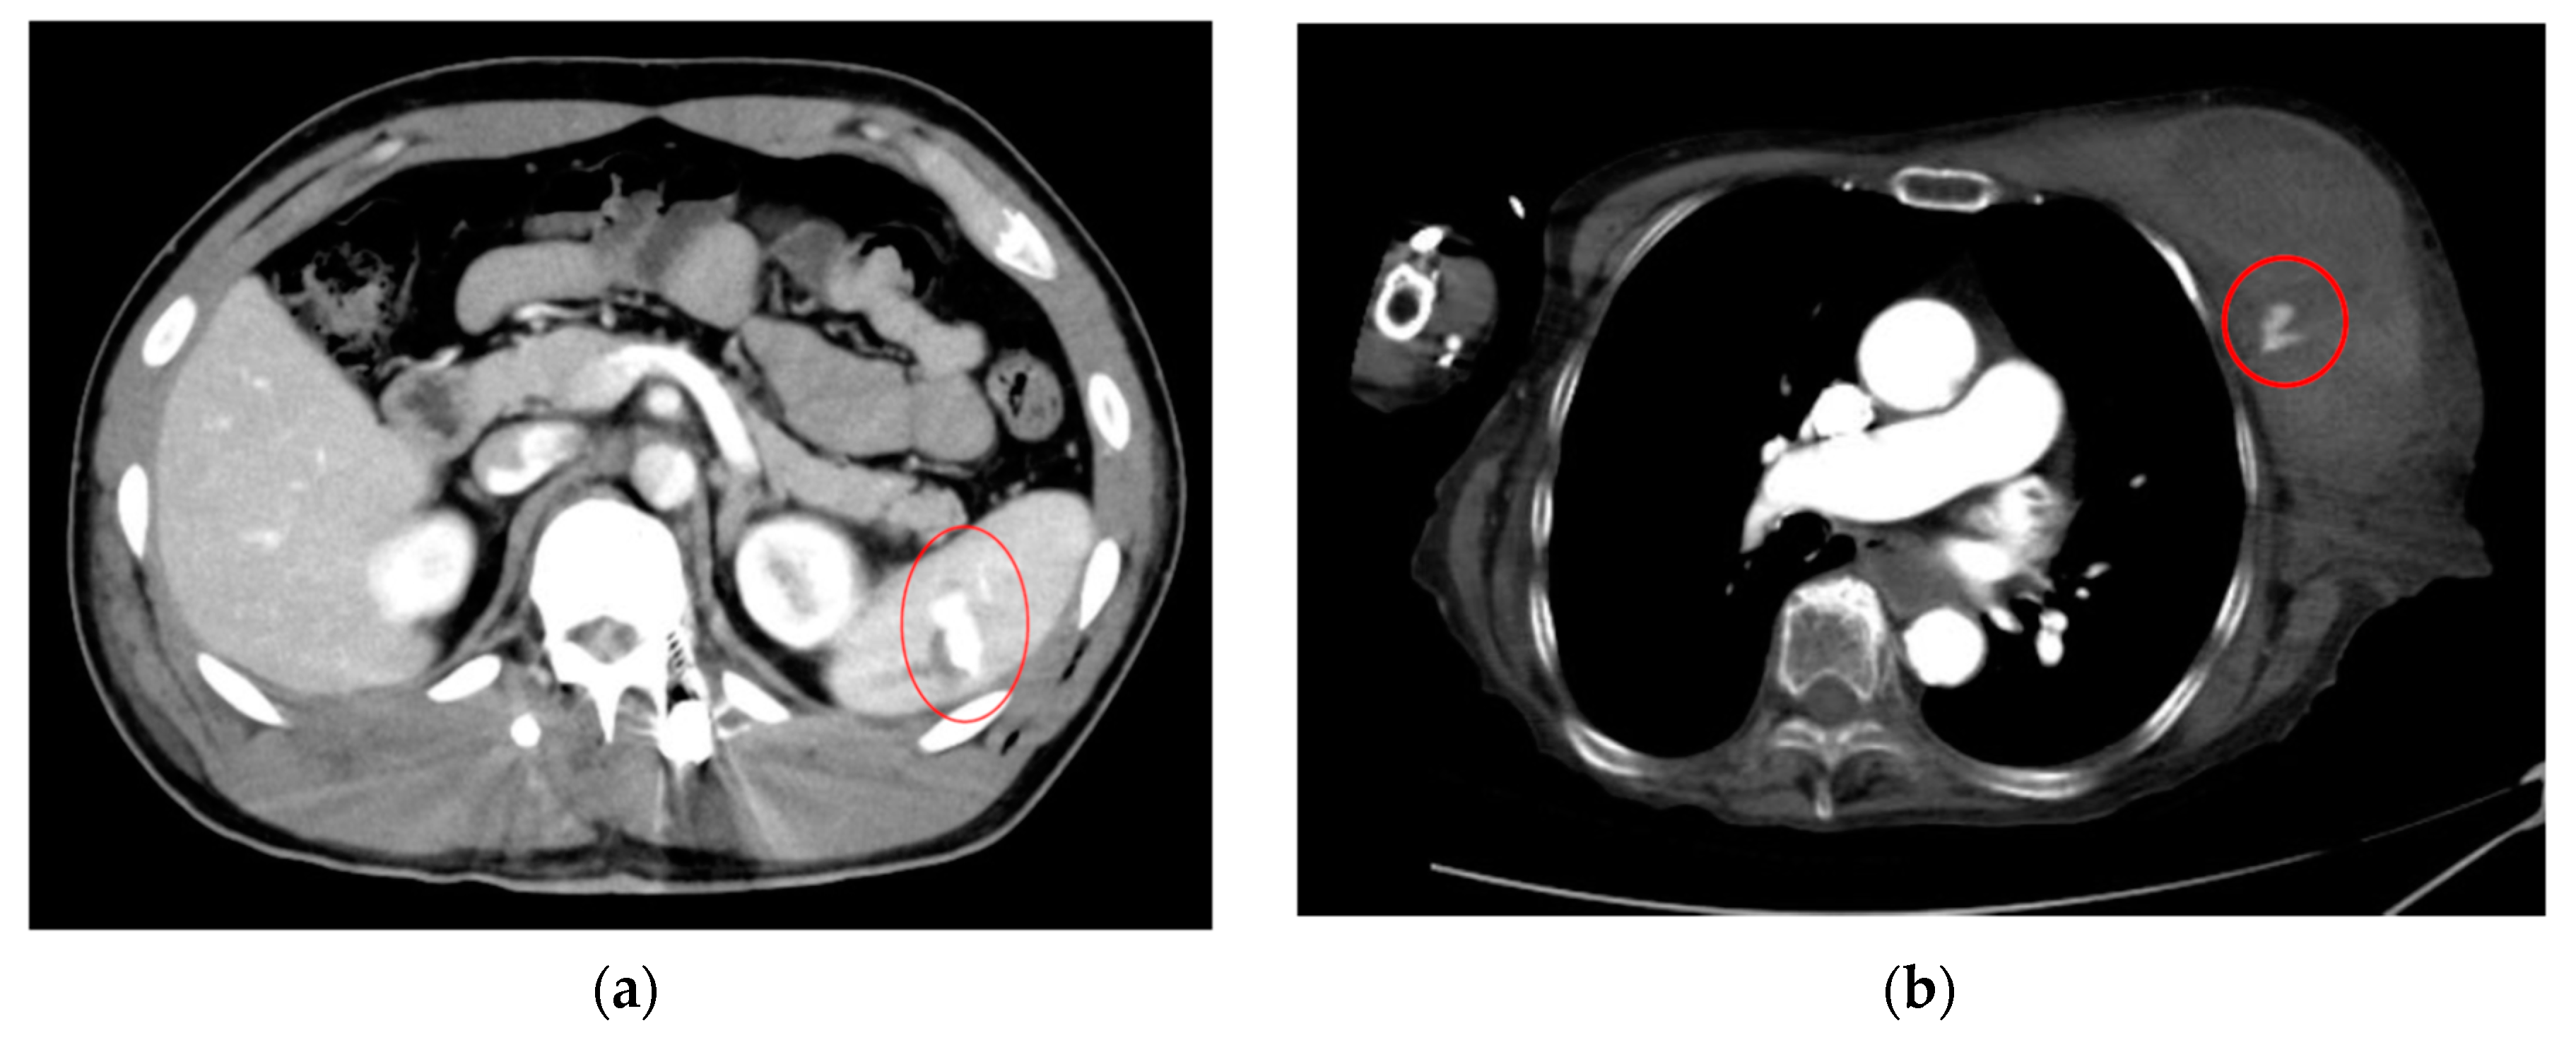

- AI for Image Analysis: AI-based image analysis algorithms can enhance the detection and diagnosis of extravasation events in imaging studies, such as ultrasound, MRI, and CT. These algorithms can automatically identify subtle signs of extravasation, assist healthcare providers in interpreting the imaging findings, and facilitate a timely intervention. This suggestion is subsequently extended as a separate discussion.

- Albano, D.; Benenati, M.; Bruno, A.; Bruno, F.; Calandri, M.; Caruso, D.; Cozzi, D.; De Robertis, R.; Gentili, F.; Grazzini, I.; et al. Imaging side effects and complications of chemotherapy and radiation therapy: A pictorial review from head to toe. Insights Imaging 2021, 12, 76. [Google Scholar] [CrossRef] [PubMed]